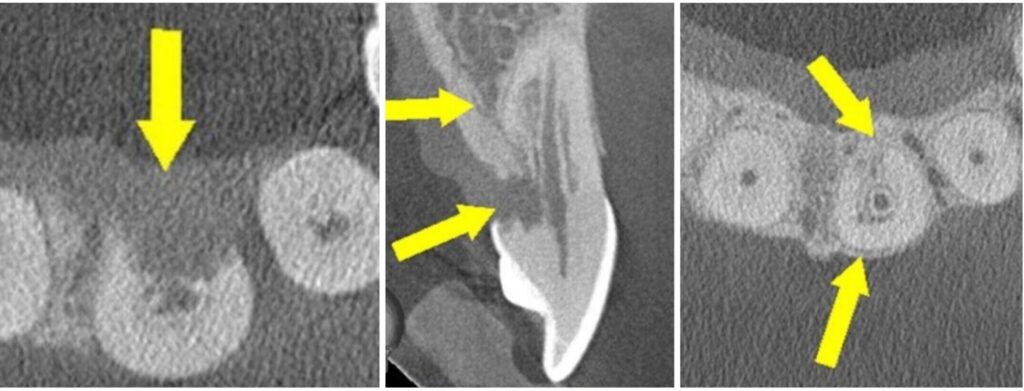

Cervical resortion: Note the apical extensions and circumpulpal spread

Then you got external resorption—that’s the real horror movie stuff. Comes from the outside, like a SWAT team takin’ the wall down. Can be:

• Cervical resorption (hides right by the gumline, throws on a disguise and pretends to be decay—sneaky little punk)